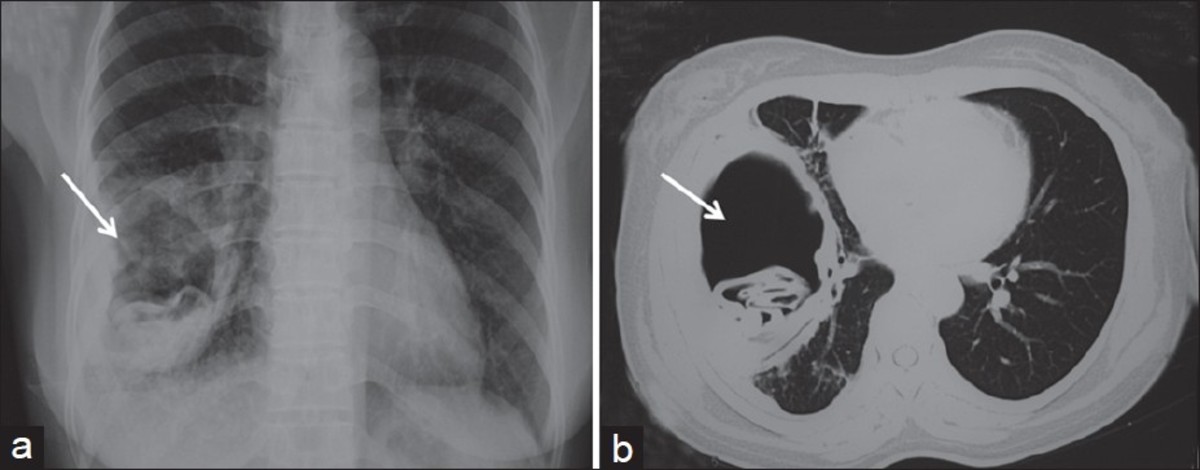

Рентген как метод диагностики легочных гельминтов у кошек: что нужно знать владельцам

Легочные гельминты у кошек – это опасные паразиты, которые могут вызвать серьезные заболевания дыхательной системы. Одним из эффективных методов диагностики является рентгеновское исследование, позволяющее выявить их наличие в легких. В этой статье мы расскажем, как этот метод помогает в диагностике и что нужно знать владельцам домашних питомцев.

Рентген может помочь не только обнаружить гельминтов, но и выявить возможные осложнения в легких.

Дирофилярии (Сердечно-легочные черви)